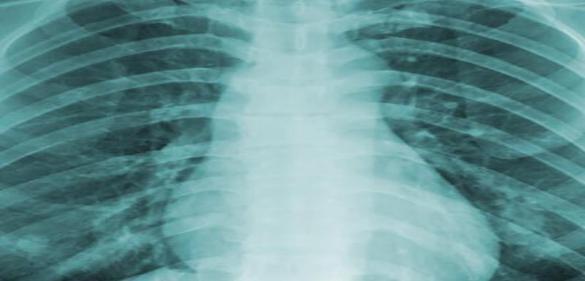

TB Radiology: Perspectives on Adult and Pediatric Radiology with Case Study Examples | Recorded April 28, 2026

Radiologists dig into the nuances of chest imaging and the different presentations of adults and children. A radiologist reviews the very challenging situation of central nervous system TB and the role of imaging in diagnosis, treatment, and evaluation.

Perspectives on Adult TB Radiology - Jennfer Febbo, M.D.

Pediatric Tuberculosis: Radiologic Considerations - James Gaensbauer, M.D, MScPH

Imaging of CNS Tuberculosis - Aaron Field, M.D., Ph.D.